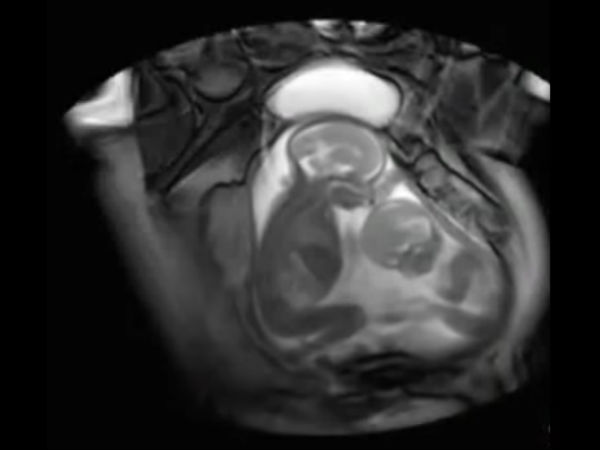

Adorable Video Of Twins Fighting In Womb!

These twins are going to be little brats, as we can see them fight in their mother's womb! Check out the crazy video and decide...

Being pregnant is a great feeling, and being pregnant with twins is even more a greater feeling along with a big responsibility. Imagine a day you walk into the clinic for a regular checkup and all that you see is that your unborn twins are having a cute little fight in the womb!

This is something very rare that was captured on camera! A doctor was using a new technology as part of a London medical study where she examined a pregnant woman and scanned to find out that the twins were actually having a cute little fight inside the womb.

The new technology that the doctor had used in this case is called cine-MRI scan; and this is done to study twin-to-twin transfusion syndrome.

This "twin-to-twin transfusion syndrome" occurs when the twins share a placenta that contains abnormal blood vessels. This is something that can cause one of the twins to get less nutrients than the other.

In this you can see the little smaller sized twin kick the bigger twin, and it looks like he/she needs his/her own space. The elder one does not retaliate initially, but gives it back soon.

Guess all this happens when the twins share the same placenta. Most of the mothers who have seen the video can relate to their children fighting to get the best spot on the couch or get the best seat.